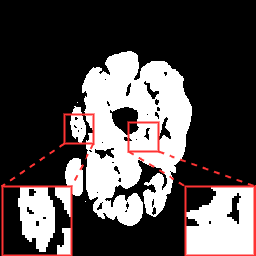

(a) Image

(b) GT

(c) Baseline

(d) Our method

(e) ResU-Net

(f) AttU-Net

(g) MC-Net

(h) Fully U

Table 1 lists the quantitative results (evaluated on the testing data) including state-of-the-art approaches for the following methods: U-Net (Baseline) [5], ResU-Net [7], AttentionU-Net [6, 22], MC-Net [15], a fully supervised U-Net, and our proposed method. Qualitative results are shown in Fig. 3. When only labeled 2D samples were available for training, the proposed method outperformed all the compared methods with an improvement of the and metrics of and when compared to the baseline. Furthermore, our method proposal with a low number of samples gave results comparable to those of a fully supervised U-Net trained with labeled samples.